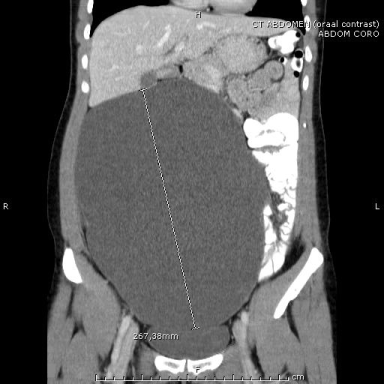

In 2006, a 26-year old female, pregnant with her first child, presented for a regular check-up. Gestational age of the child was nineteen weeks. During routine US, a space occupying lesion was discovered next to the uterus with a size of 15 x 12 x 6 cm, transonic, with bright echo density, initially diagnosed as a pathologic cystic lesion of the right ovary. However, as there were no other findings supporting a malignant diagnosis, tumor markers CEA, alfa-fetoprotein and CA125 were within normal range, and the intra-uterine pregnancy was intact, watchful waiting was indicated. Over twenty weeks later, the patient delivered a healthy female baby after a spontaneous, uncomplicated childbirth. Several weeks following delivery the patient was examined and was found to have normal internal genitalia; therefore, in February 2007 abdominal MRI with gadolinium was performed, showing a sharply demarcated additional structure, with a hypo-intense dimension on T1-weighed haste and highly hyper-intense dimension on T2 weighed haste, with no contrast uptake of gadolinium. It was defined a cystic lesion, most compatible with a benign mesenteric cyst (Figure 1). Therefore, the patient was referred to the surgeon in order to arrange total cyst resection by laparotomy. Due to personal circumstances, including a second pregnancy, the operation was postponed for many years. In 2013, the patient returned to department of surgery with complaints of symptomatic abdominal distention, specifically on the left side of the abdomen. These complaints have been present for a few months and are slowly progressive. She has no complaints of pollakiuria or urgency. By this time, she reached the age of 32 and had no accompanying symptoms such as weight loss or malaise. A CT scan was performed, showing progressive growth of the cystic mass, with compression of the bladder (Figure 2). Apart from the progressive growth, there were no signs of malignant transformation, invasion of other organs or lymfadenopathy.

Figure 1: Coronal T2 Weighted Haste (TE/TR/FA=60ms./1100ms./150°)

MRI scan showing a large cyst of 21x11x16cm. The uterus is shifted to the

left by the cyst, while the small intestine is moved to the upper left quadrant.

At this time, the patient didn’t have any symptoms.